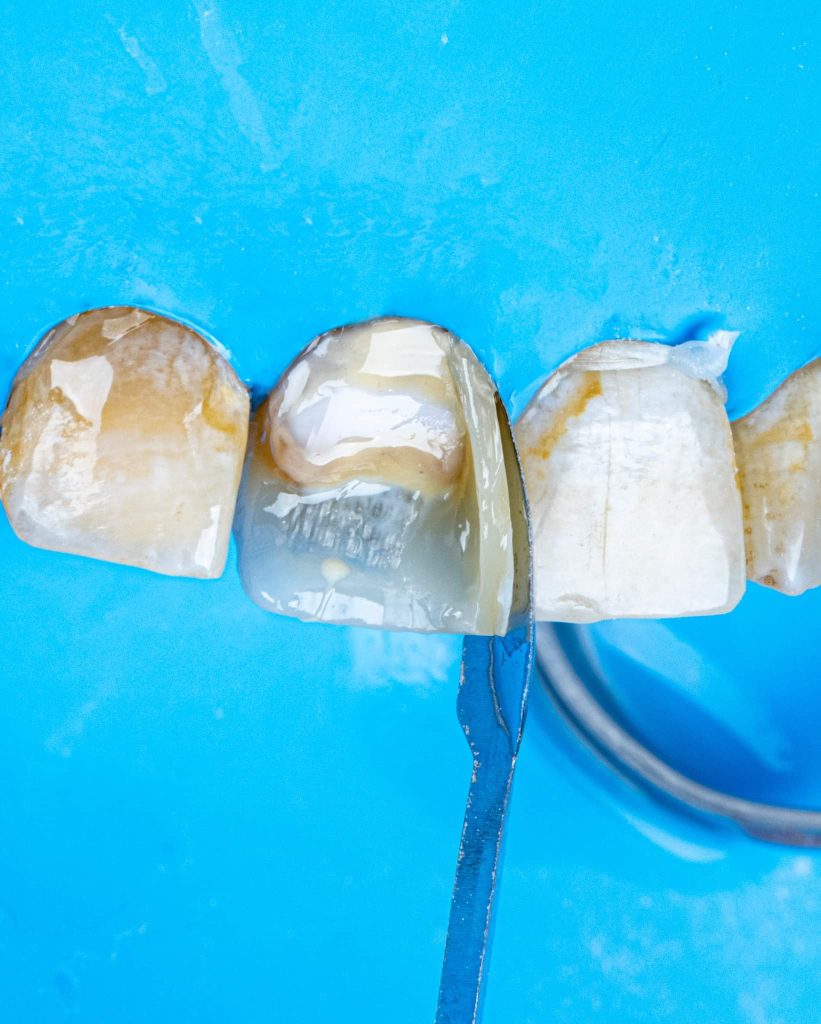

1.Masking the discoloration: This is where one or several shades of composite resin are used to camouflage the underlying darkened tooth shade. For severe discolorations, a resin-based opaque layer placed over the discolored areas of tooth may be required. This is then covered with dentine and enamel shades to match the adjacent teeth.

After discussing the treatment options with the patient, he chose the direct composite veneer. The treatment included endodontic treatment, internal bleaching, direct composite veneer for the right central, and aesthetic reshaping for the laterals and left incisor also by composite restoration. The case completed in 2 sessions.